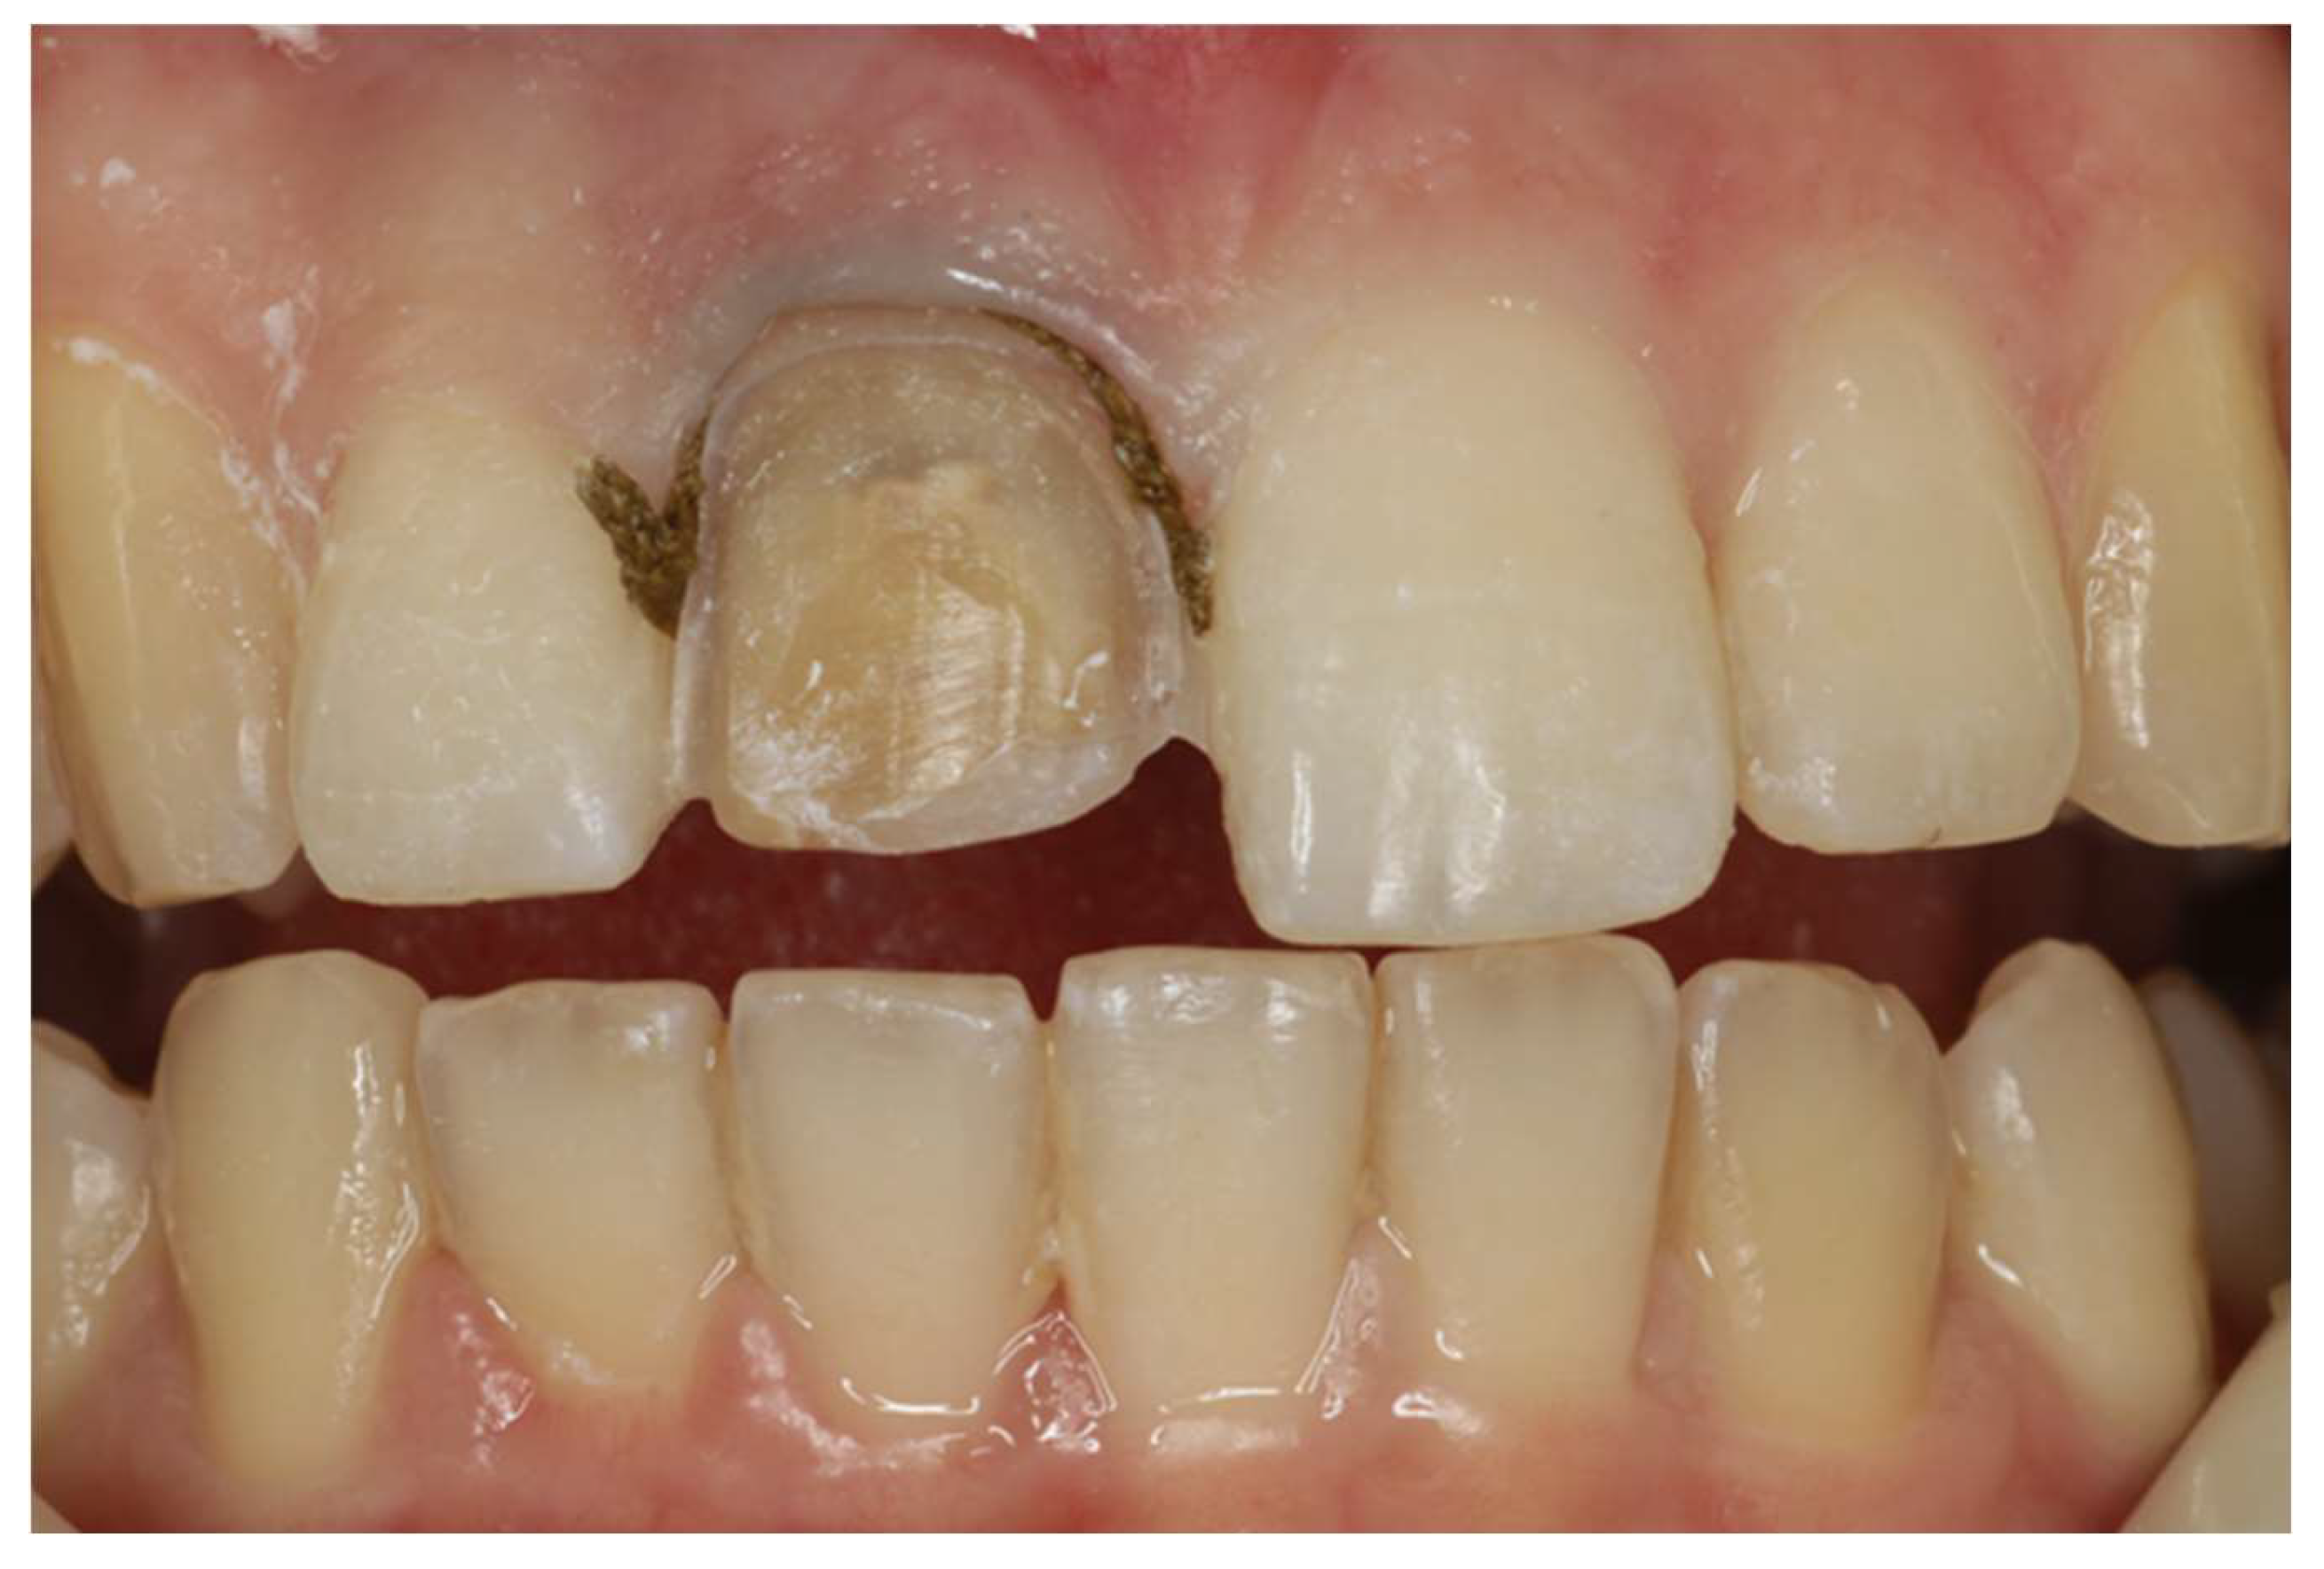

2. Clinical Case

- Considering bonding and cementation, adhesively cemented high translucency monolithic zirconia seems to be a suitable option for veneers.